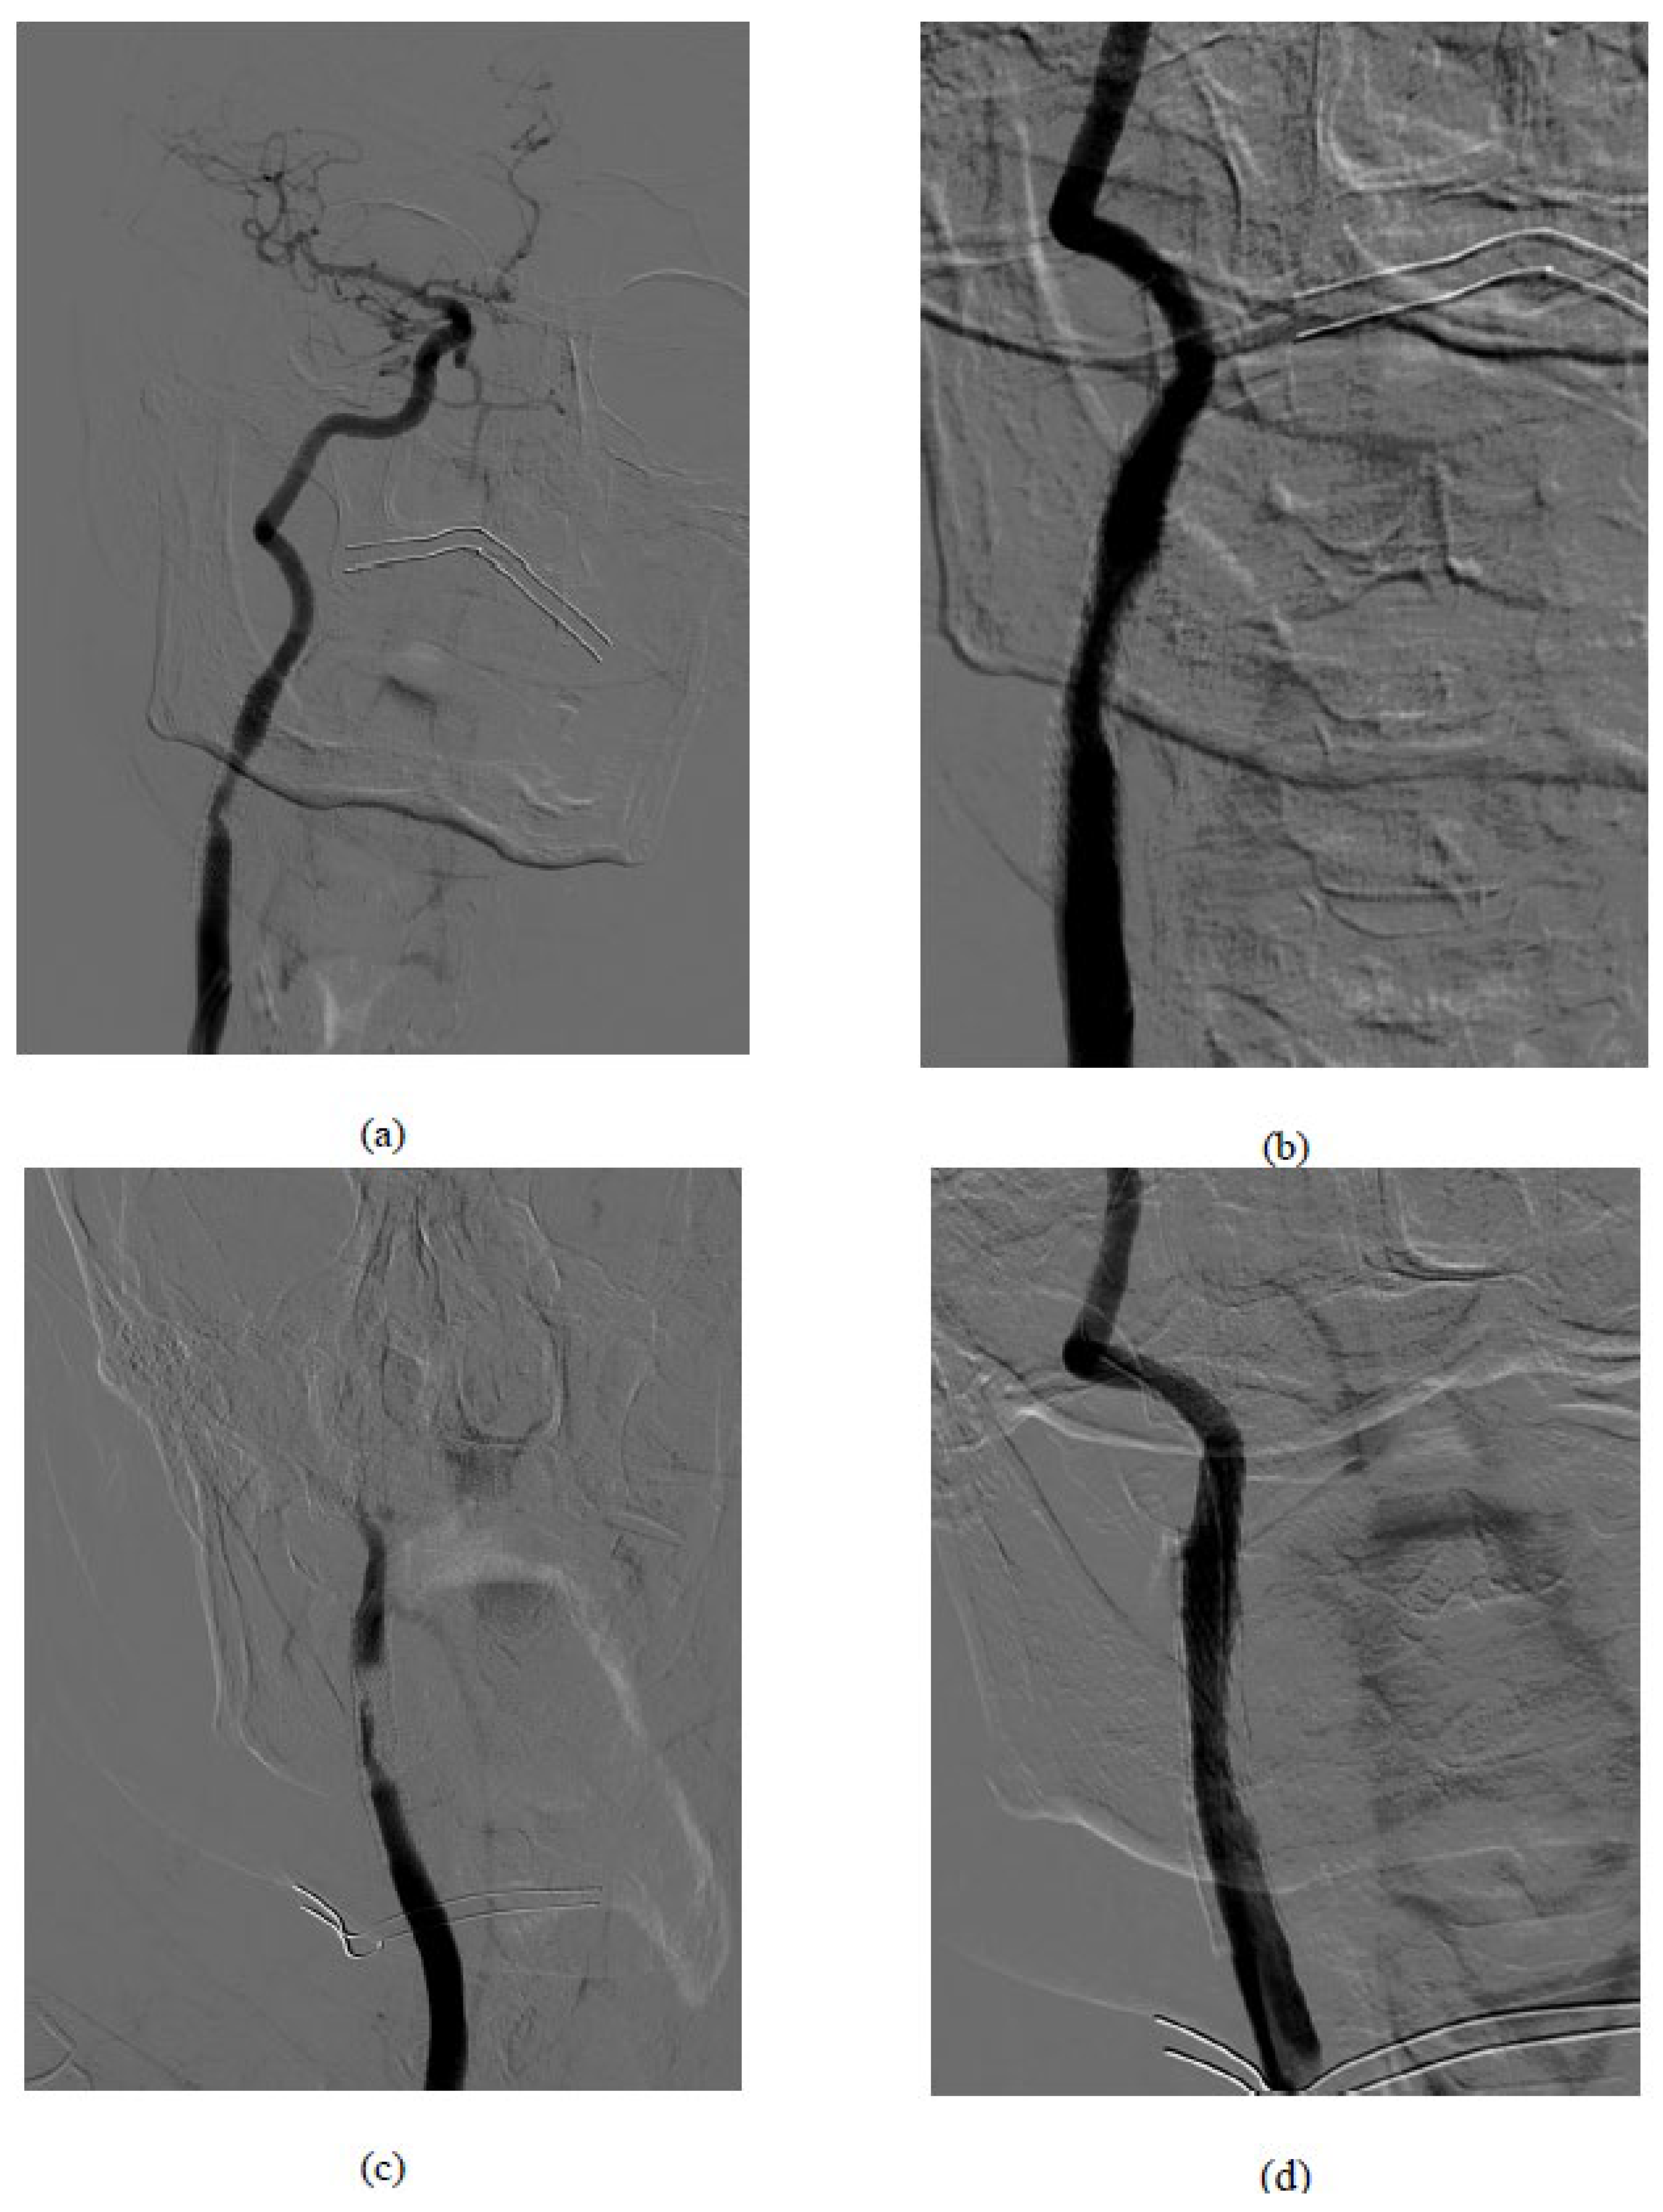

Figure 1. Procedural images: (a) basal symptomatic in-stent restenosis (b) result after drug-coated balloons (c) acute carotid stent thrombosis after the DEBalloon (d) Final result after CGuard MicroNet-covered stent implantation.

Medication was the dual platelet, including AAS and Clopidogrel. 5000 IU Heparine was given with ACT control pre intervention. Using an ultrasound-guided approach of the right common femoral, a 5F catheter (Terumo) was used to engage the right common carotid. With a curved 260 cm stiff guide (Terumo), a 40° Mach1 (Boston Scientific) guiding catheter was advanced proximal to the ISR. Angiographic control confirmed the presence of tight diffuse ISR affecting most of the stent length. After positioning the Epi-filter cerebral protection system (Boston Scientific), a dilation was performed with a 4 mm medicated balloon device (DCB) at the level of the restenosis. At the end of the procedure, the filter was removed, and the optimal restoration of the vessel lumen was documented without evidence of filling defects. The patient was assigned in good health to the recovery area.

Unexpectedly, ten minutes later, the patient initiates a state of confusion along with left hemiplegia, deviation of the gaze, and the buccal rim. The neurological evaluation informed an NIH score of 21. The immediate angiographic control documented acute in-stent thrombosis and slow-flow compromising the ipsilateral intracranial circulation.

To tackle this emergency, an Epi-filter cerebral protection system was again placed, and a 9 x 40 mm micromesh stent (CGuard, InspireMD) was released slightly downstream from the end of the stenosed stent and gently post-dilated with a 5 mm balloon. The control angiography showed a resumption of the internal carotid flow with regular visualisation of the intracranial circulation.